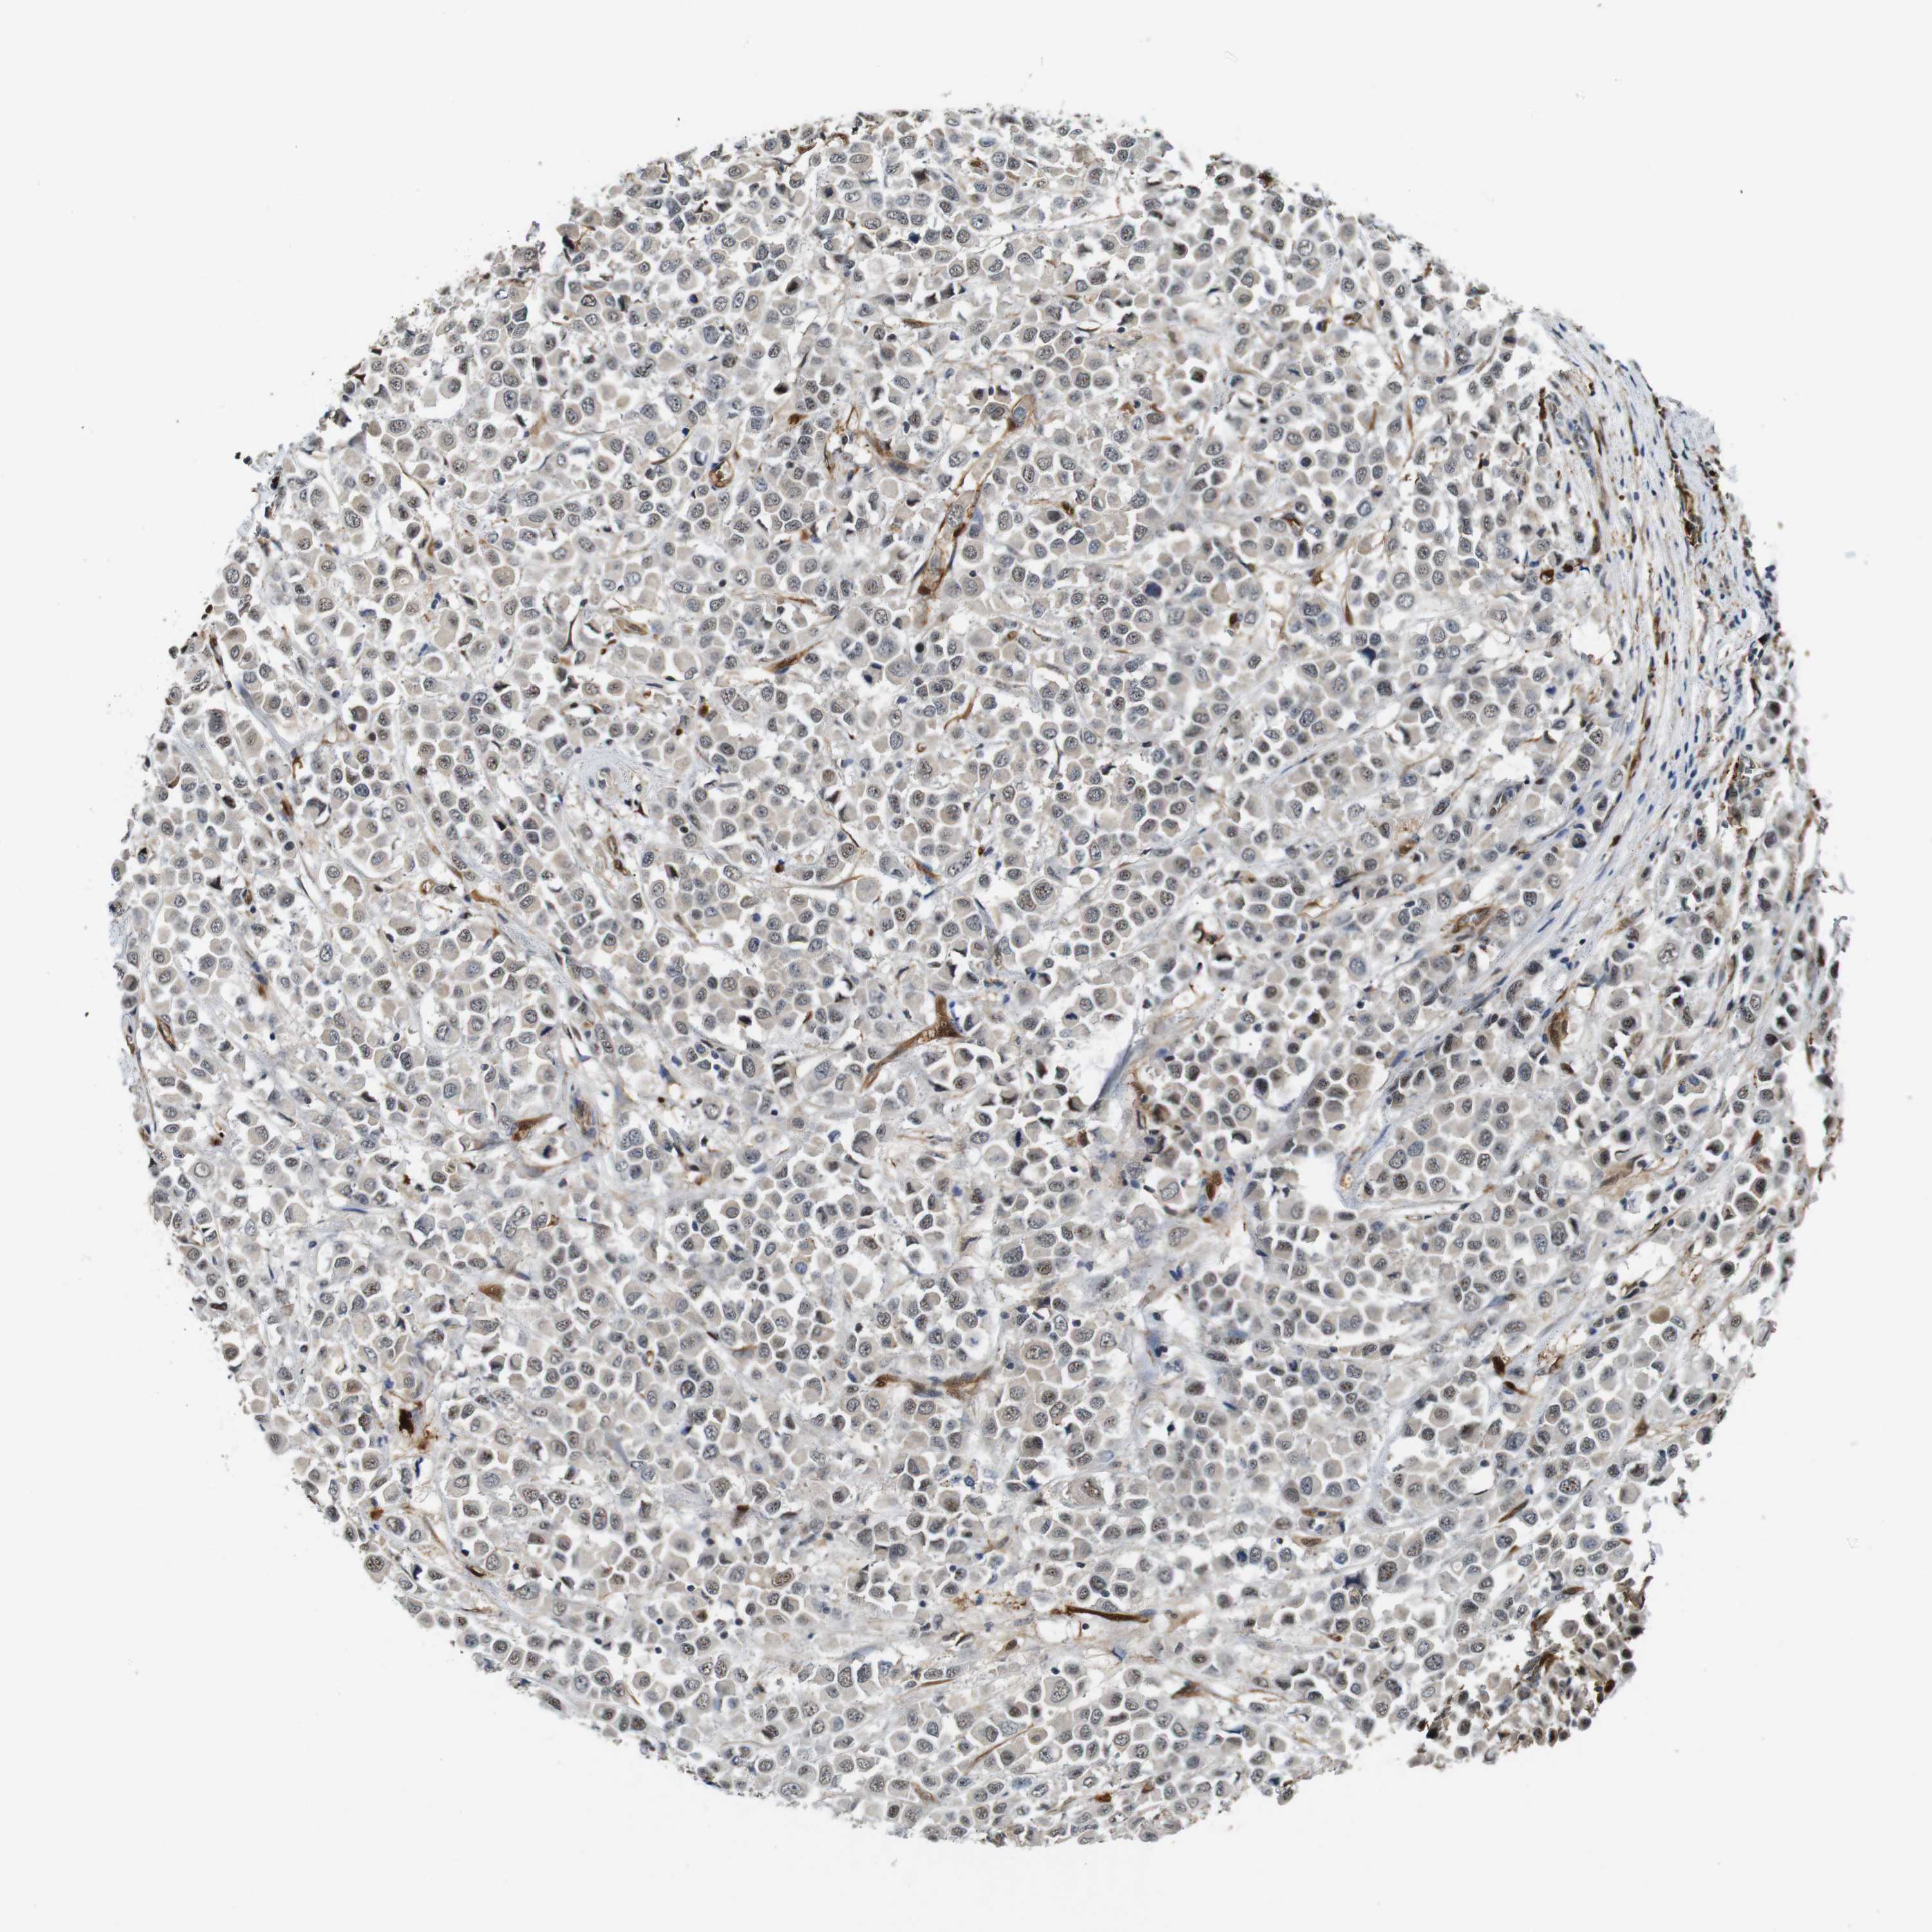

CANCER BREAST CANCER Show tissue menu

BRCA TCGA BRCA VALIDATION PROTEIN EXPRESSION